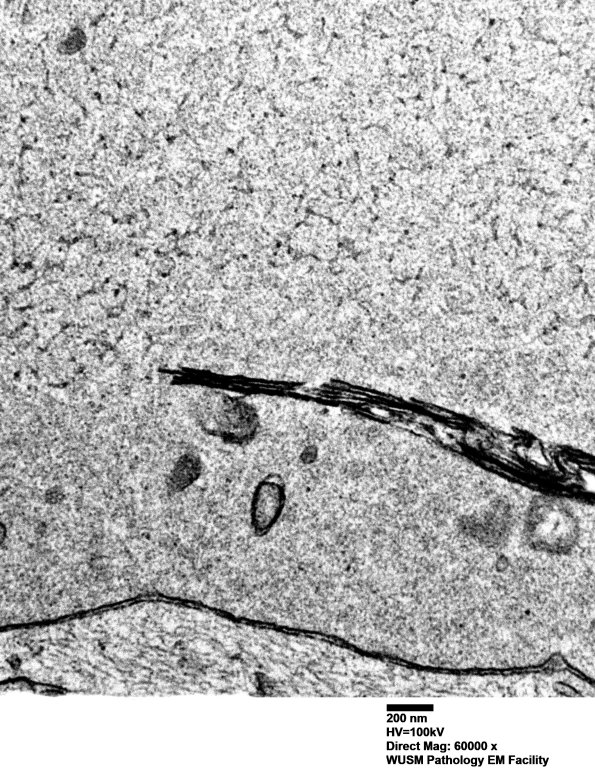

Shown is a large axon with dense axoplasm, tubulovesicular elements and a membranous cleft. (electron micrographs)